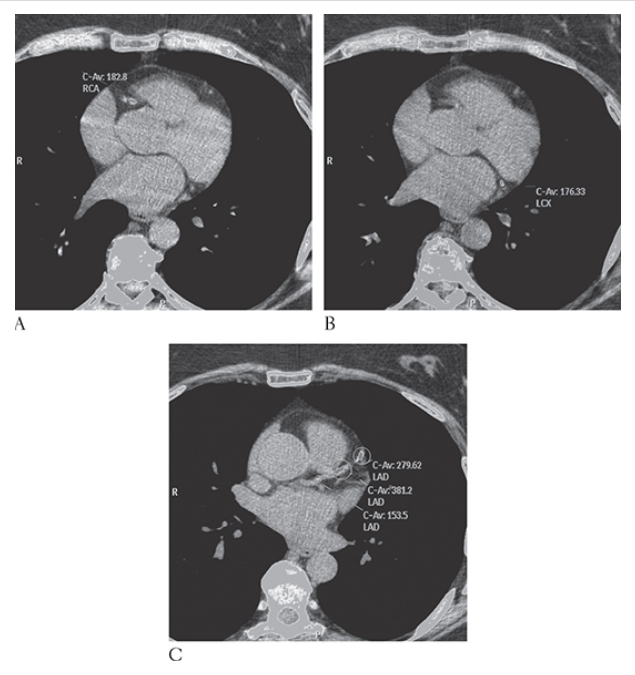

Coronary Artery Disease. Nonenhanced CT (NECT) shows computer-aided detection and calculation of coronary artery calcification in the right coronary artery left circumflex artery

Coronary Artery Disease. Nonenhanced CT (NECT) shows computer-aided detection and calculation of coronary artery calcification in the right coronary artery and left anterior descending coronary artery

Coronary Artery Disease. Nonenhanced CT (NECT) shows computer-aided detection and calculation of coronary artery calcification in the right coronary artery